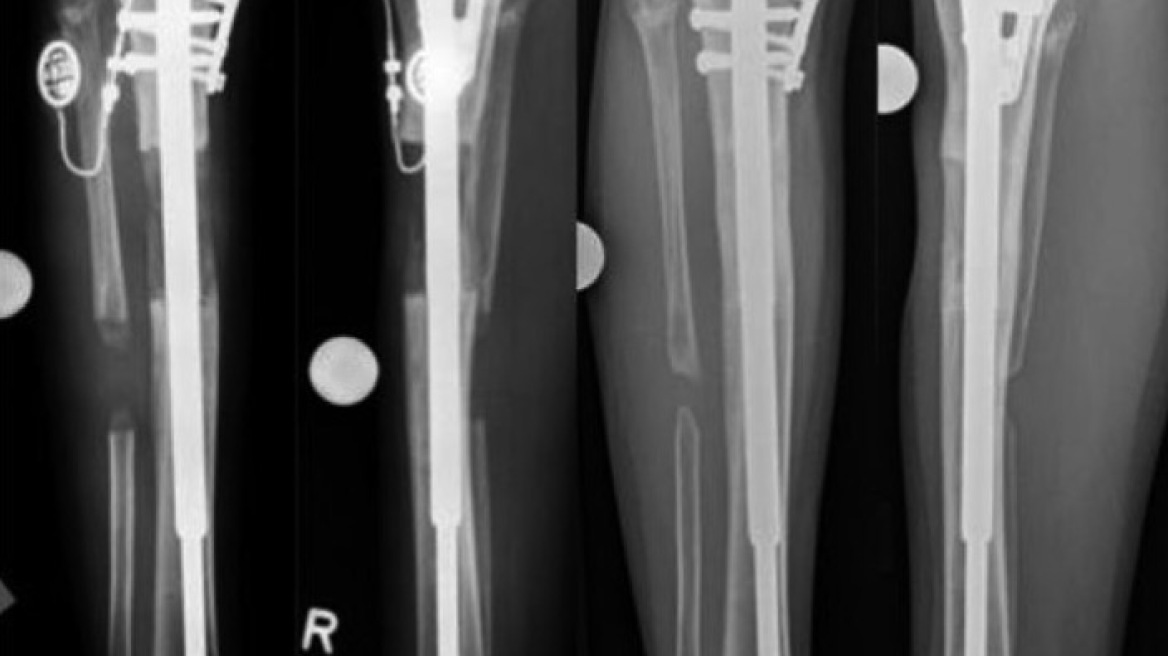

Αννα Λεντή: Και βέβαια μπορούμε . Και μπορούμε χάρη στην τεχνική της οστικής επιμήκυνσης  που αποτελεί μία από τις εφαρμογές της Διατατικής Οστεογένεσης. Βασίστηκε στην παρατήρηση ότι εάν ένα οστό υποστεί οστεοτομία, δηλαδή «σπάσει» ελεγχόμενα στο χειρουργείο και τα άκρα του απομακρυνθούν το ένα από το άλλο με έναν σταθερό ρυθμό, της τάξης του 1 χιλιοστού την ημέρα, τότε στο «κενό » δημιουργείται νέο οστό.

Άννα Λεντή: αρχικά όπως αναφέραμε δημιουργούμε ένα ελεγχόμενο κάταγμα στο οστό που θέλουμε να επιμηκύνουμε . Ακολουθεί μια διαδικασία δύο φάσεων.  Στη πρώτη φάση  γίνεται η αύξηση του μήκους και αφού φτάσουμε στο επιθυμητό μήκος οστού,  ακολουθεί μία νέα περίοδος αναμονής, κατά την οποία το νέο οστό αποκτά Μηχανική Αντοχή. Στην φάση αυτή , το οστό ΔΕΝ είναι σε θέση να υποστηρίξει το βάρος του ασθενούς για τον λόγο αυτό , το οστό χρειάζεται να υποστηρίζεται από συσκευή ή σύστημα. Εάν η «συσκευή- σύστημα » αφαιρεθεί το οστό θα υποχωρήσει. Το βάρος λοιπόν του ασθενούς, το υποστηρίζει το «σύστημα», ενώ το οστό αναδομείται με την «ησυχία» του.

Άννα Λεντή: Ναι υπάρχουν . Η πιο διαδεδομένη τεχνική είναι αυτή κατά την οποία  εφαρμόζεται στον  ασθενή  ένα κυκλικό μεταλλικό εξωτερικό σύστημα ( σύστημα Ilizarov) . Υπάρχουν και πιο σύγχρονες μέθοδοι όπως εξάποδες πλατφόρμες  TSF/SUV ή τεεχνική LOΝ) ενώ απο τα πλέον σύγχρονα συστήματα επιμήκυνσης είναι οι αυτοματοποιημένοι ενδομυελικοί ήλοι ( motorized nails ISKD, FITBONE, PRECICE) που εμφυτεύονται μεςα στον αυλό του οςτού. Η απόφαση για το ποιό σύστημα θα χρησιμοποιηθεί τελικά εξατομικεύεται για κάθε περίπτωση ώστε να επιτευχθεί το επιθυμητό αποτέλεσμα. Οπωσδήποτε οι οικονομικοί λόγοι είναι επίσης ουσιαστικοί , καθώς τα νέα συστήματα είναι αρκετά ακριβά.